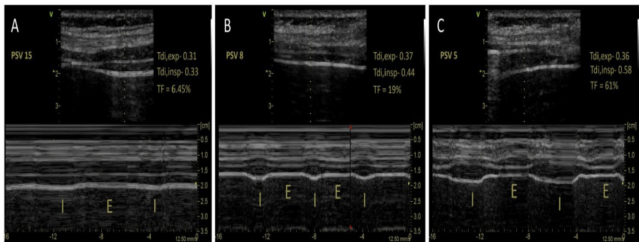

膈肌增厚率(TF)定义为吸气过程中Tdi变化的百分比:[(Tdi,span)−(Tdi,exp)/(Tdi,exp)]×100。我们通过Tdi来反映膈肌萎缩情况,而TF可代表膈肌吸气活动(努力)的程度。临床上,我们一般定义膈肌功能障碍为膈肌偏移<10~11 mm或TF<20%。

首先为支持力度的设定,一般选择通过监测患者的膈肌超声,来监控患者的吸气努力程度和所对应的支持水平。根据TF来滴定合理的呼吸支持水平,可以作为当前提出的膈肌保护性通气的一种重要手段。一般我们维持TF在15%~30%之间的呼吸支持水平作为较合适的值。TF过高,应适当提高支持水平或增加镇静/肌松的强度;若TF过低,应降低支持水平或减轻镇静/肌松的强度。

图片

图A中TF减少提示过度的支持(PS 15 cmH2O),图B中理想TF为一个较好的支持水平(PS 8 cmH2O),图C中TF增加,代表支持不足(PS 5 cmH2O